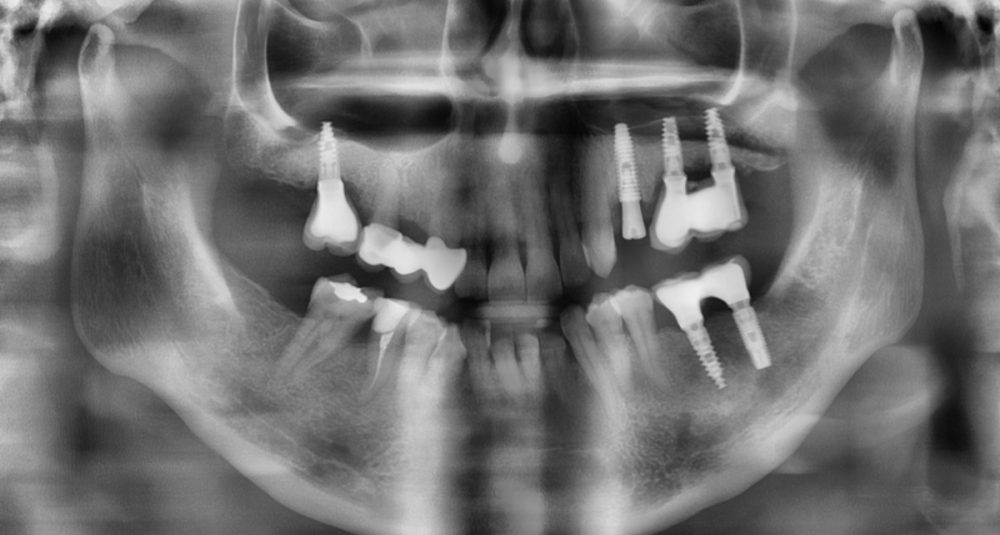

Irouil Опубликовано 8 августа, 2023 Автор Поделиться Опубликовано 8 августа, 2023 Ссылка на комментарий

АнтонТЛТ Опубликовано 8 августа, 2023 Поделиться Опубликовано 8 августа, 2023 Лучше прицельные снимки делать, на таких не рассмотреть ничего. Форум сильно сжимает изображение. Либо кадрировать эти снимки. Почему тибейсы такие короткие используются? Ссылка на комментарий

Irouil Опубликовано 9 августа, 2023 Автор Поделиться Опубликовано 9 августа, 2023 @АнтонТЛТ думаете короткие ти бейсы могут повлиять? Я сейчас не про пассивность. Лаба работает вообще с большим количеством нареканий, самое смешное в этом то, что она наша)) @NazranDantist согласен, есть риски, что какие-то сели внатяг. Ссылка на комментарий

АнтонТЛТ Опубликовано 9 августа, 2023 Поделиться Опубликовано 9 августа, 2023 Разве что короткие тибейсы могут упираться в ткани. Фдм какого диаметра используются на молярах? Ссылка на комментарий